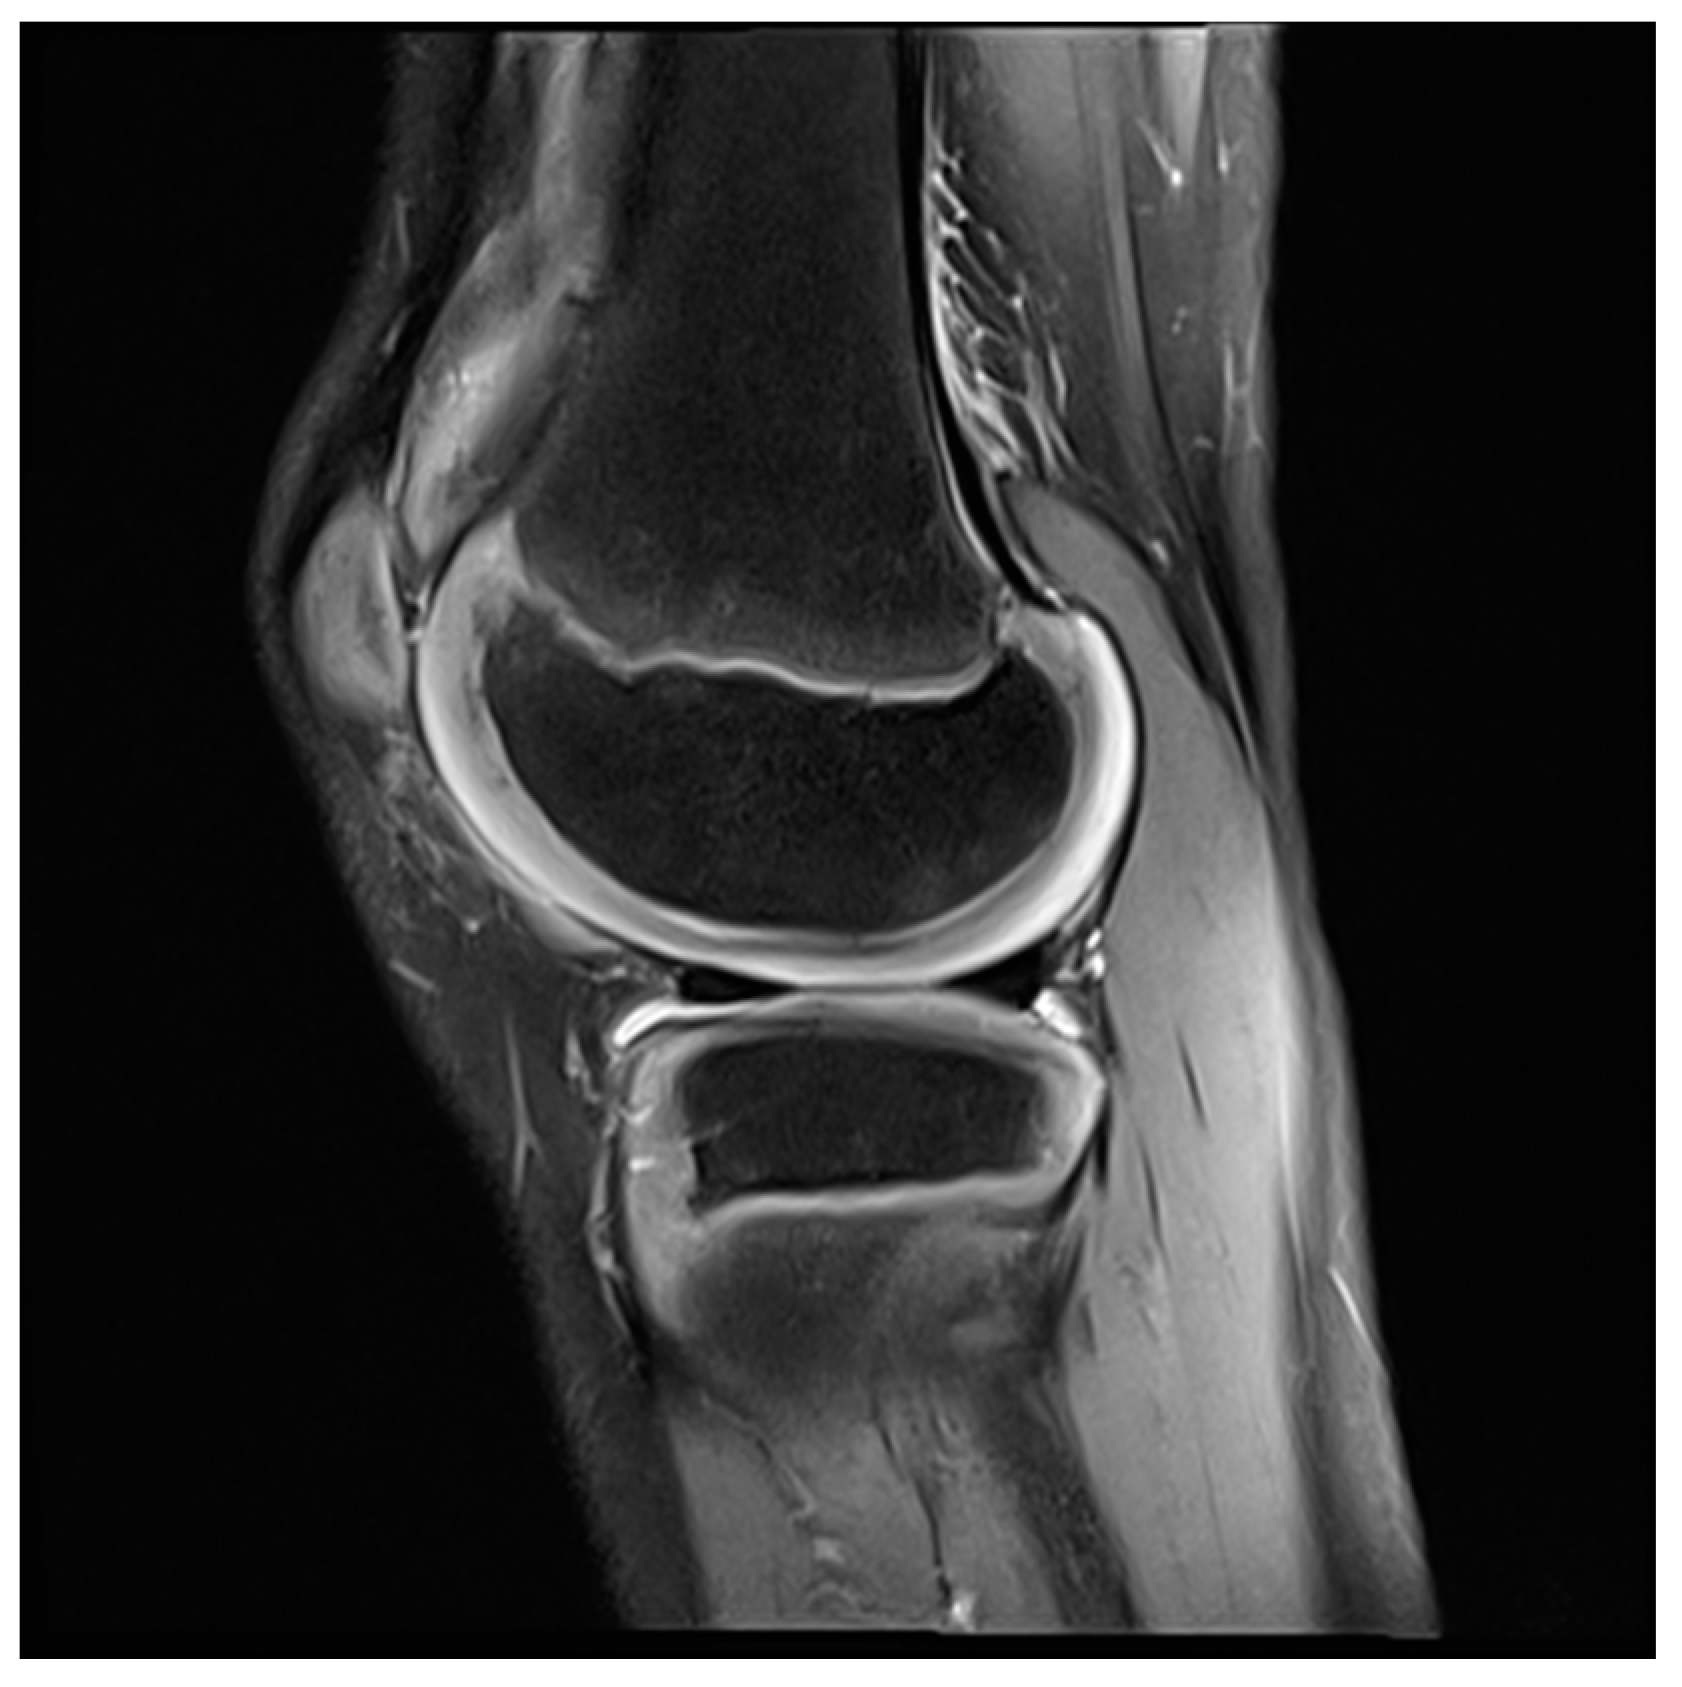

- Hirose, J.; Nishioka, H.; Tsukano, M.; Matsubara, S.; Usuku, K.; Mizuta, H. Matrix changes in articular cartilage in the knee of patients with rheumatoid arthritis after biological therapy: 1-year follow-up evaluation by T2 and T1ρ MRI quantification. Clin. Radiol. 2018, 73, 984.e911–984.e918. [Google Scholar] [CrossRef]

- Maderbacher, G.; Greimel, F.; Schaumburger, J.; Grifka, J.; Baier, C. The knee joint in rheumatoid arthritis-current orthopaedic surgical treatment options. Z. Rheumatol. 2018, 77, 882–888. [Google Scholar] [CrossRef] [PubMed]

- Carl, H.D.; Gelse, K.; Swoboda, B. Total knee arthroplasty for rheumatoid arthritis. Z. Rheumatol. 2011, 70, 411–416. [Google Scholar] [CrossRef]